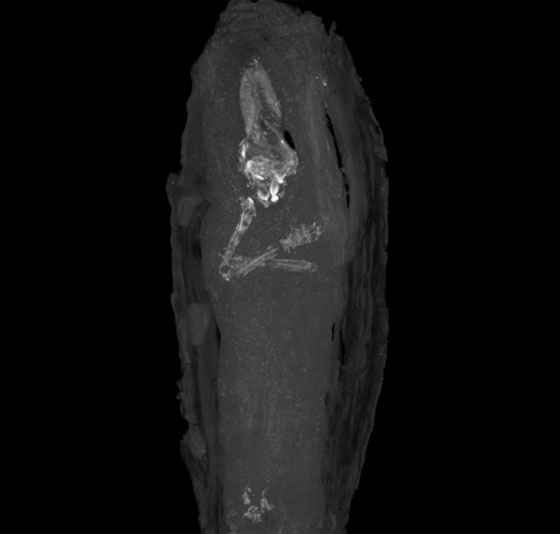

ولم يكشف تصوير الأشعة التقليدية عن حقيقة ما تحتوية اللفافة طيلة هذه السنين، حتى نجح العلماء في الكشف عن هذا السر باستخدام تقنية التصوير الطبقي المبرمج المكروي أو X-ray microtomography وهي تقنية تستخدم أشعة إكس لإنشاء مقاطع عرضية في الأجسام ثلاثية الأبعاد دون الحاجة لتحطيمه.

ولم يتسن للعلماء تحديد نوع الجنين، كما أن جمجمته كانت خاوية من محتوياتها، إلا أن أصابع القدمين واليدين تم التعرف عليها بسهولة، فيما كان الذراعين متقاطعين فوق الصدر، في دلالة على عناية كبيرة في عملية التحنيط تعزز منها طريقة زخرفة التابوت.